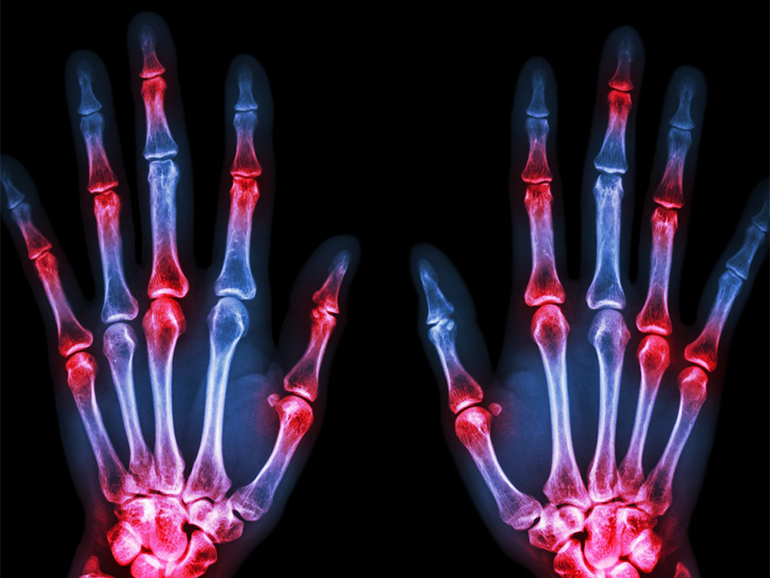

The focus of rheumatology is the joints, soft tissues, autoimmune illnesses, and heritable connective tissue disorders. It is a subspecialty of internal medicine. A rheumatologist is a medical professional who focuses on the diagnosis, therapy, and treatment of rheumatic disorders.

Rheumatology is a medical specialty in which the diagnosis and treatment require invasive techniques. But lately, scientists have been developing techniques to treat rheumatological diseases through non-invasive techniques.